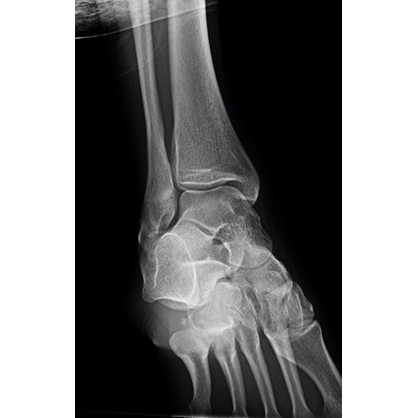

Independent interpretation of knee radiographs obtained at initial presentation in the ED were concerning for possible subluxation of the fibular head, with no acute fracture noted. Given the concern for high ankle sprain, radiographs of the right ankle with stress views were obtained in clinic which demonstrated a congruent ankle mortise with no acute fracture or evidence of instability on stress views Case Photo #5 . In addition, an MRI of the right knee without contrast was obtained which demonstrated full thickness tearing of the posterior tibiofibular ligament from its fibular attachment, partial tearing of anterior tibiofibular ligament, a small effusion of the proximal tibiofibular joint, and slight subluxation of the fibular head consistent with tibiofibular joint instability, with no fracture or chondral injury Case Photo #6 [Photo7].